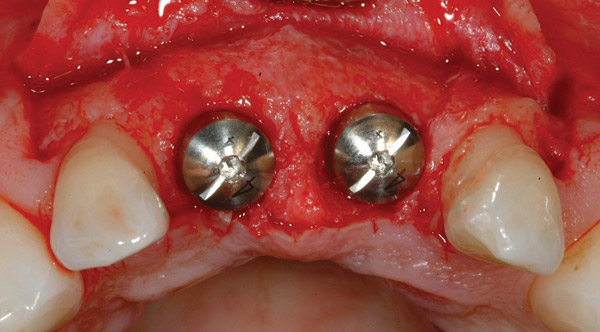

Figure 10  Temporary healing abutments are placed immediately following extraction of teeth 8 and 9. Note that there is no damage to the surrounding periodontium due to atraumatic extractions.

Figure 10